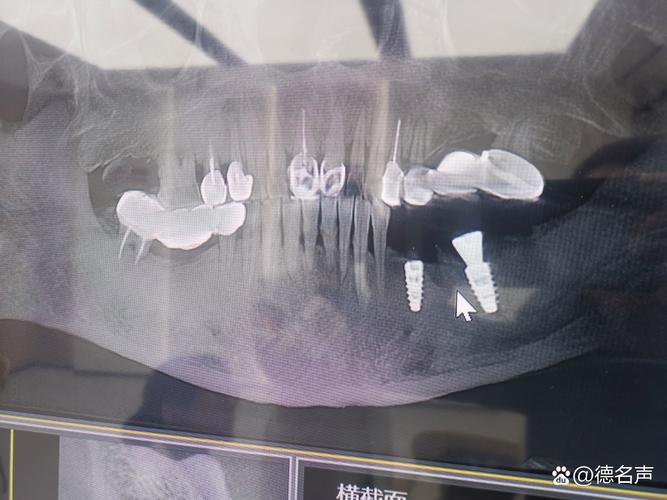

拍完CT后,医生会通过专业软件(如Dexis、ImplantStudio)进行三维重建,在电脑上“模拟”种植过程:

- 测量骨量:精确标记缺牙位置的骨高度、宽度,计算能否满足种植体直径(常用3.5-5.0mm)和长度(8-16mm)的需求;

- 设计种植路径:避开神经管、上颌窦等重要结构,确定种植体植入的角度、深度;

- 评估骨密度:判断骨质类型(Ⅰ类密质骨愈合快,Ⅳ类疏松骨可能需要植骨);

- 制定方案:如果骨量充足,直接设计种植方案;如果不足,同步规划植骨类型(如自体骨、骨粉)、上颌窦提升等方案。